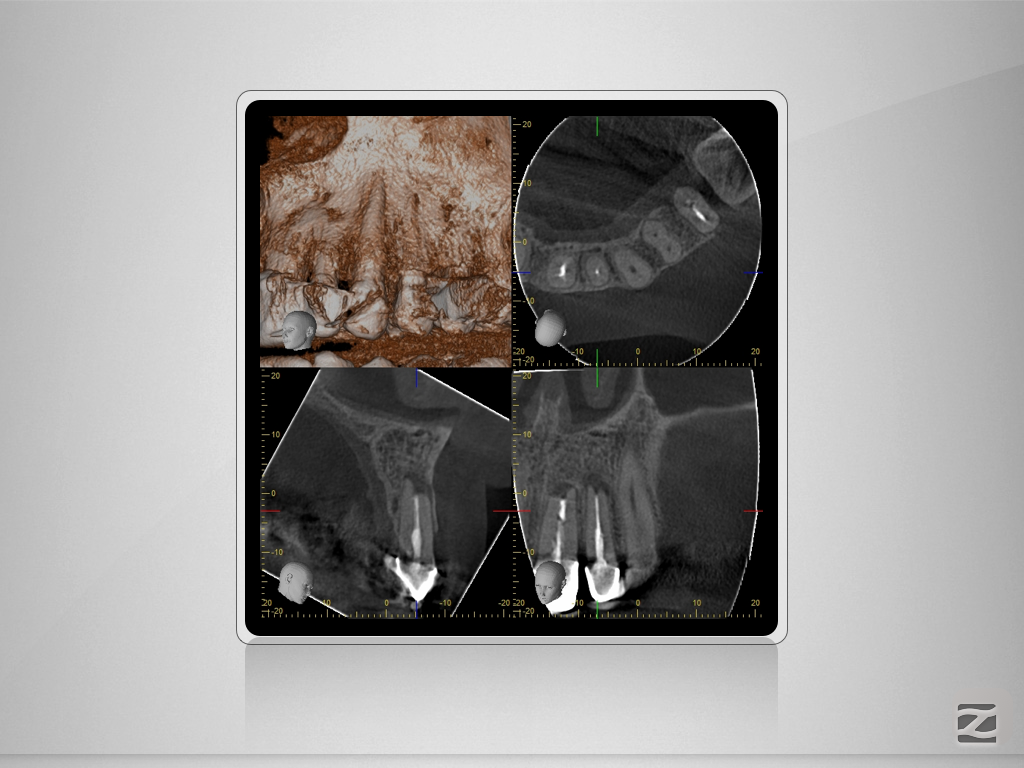

21,22D.003

Große periapkale Lyse und CaOH2-Extrusion